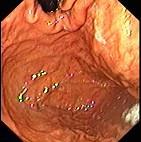

问题 女,54岁,腹胀、嗳气4个月余,无腹痛、反酸、恶心、呕吐,一般情况良好,二便正常,查体无异。B超肝胆无异常,胃镜检查如图,最有可能性的诊断是 ( )

选项 A.神经性嗳气 B.消化性溃疡 C.慢性胃炎 D.慢性胰腺炎 E.胃癌

答案 A